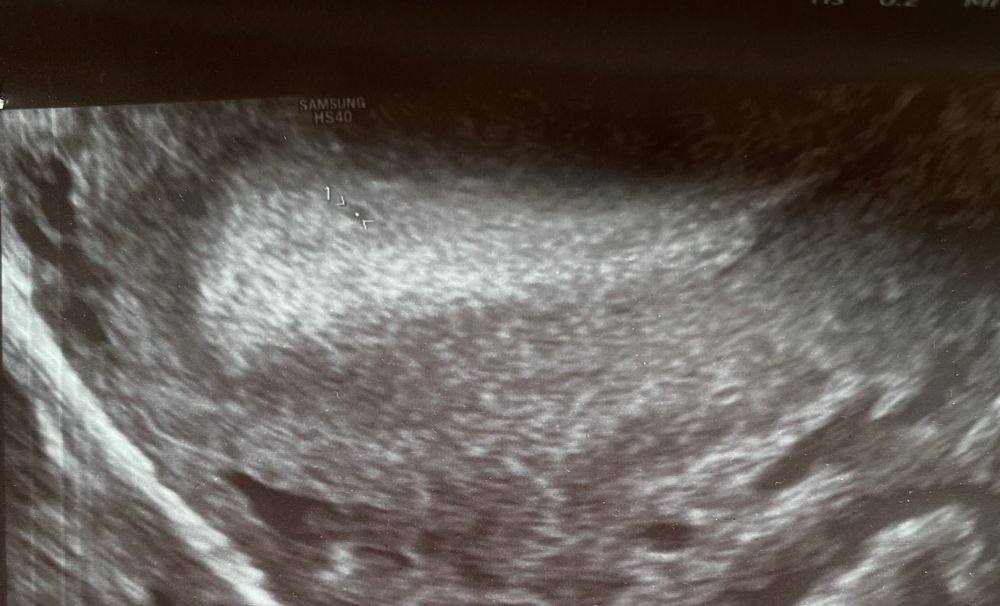

УЗИ И ПЯ ИЛИ ЧТО 😤

Знаете, лично я не вижу ЖТ, но вижу фоликулярную кисту или просто большой ДФ. ПЯ не вижу, просто может быть узелок, полипчик, складка, пузырёк воздуха, сгусток кровки и др.